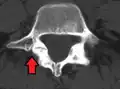

Anterolisthesis L5/S1

Anterolisthesis L5/S1. Blue arrow normal pars interarticularis. Red arrow is a break in pars interarticularis.

Isthmic anterolisthesis is where there is a defect in the pars interarticularis.[12] It is the most common form of spondylolisthesis; also called spondylolytic spondylolisthesis, it occurs with a reported prevalence of 5–7 percent in the US population. A slip or fracture of the intravertebral joint is usually acquired between the ages of 6 and 16 years, but remains unnoticed until adulthood. Roughly 90 percent of these isthmic slips are low-grade (less than 50 percent slip) and 10 percent are high-grade (greater than 50 percent slip).[9] It is divided into three subtypes:[13]

Computed Tomography (CT)

Computed tomography can be helpful in evaluating bony vertebral abnormalities, such as fractures.[33] This can be helpful in determining if the fracture is a new, old, and/or progressing fracture.[33] CT use in spondylolisthesis evaluation is controversial due to high radiation exposure.[34]